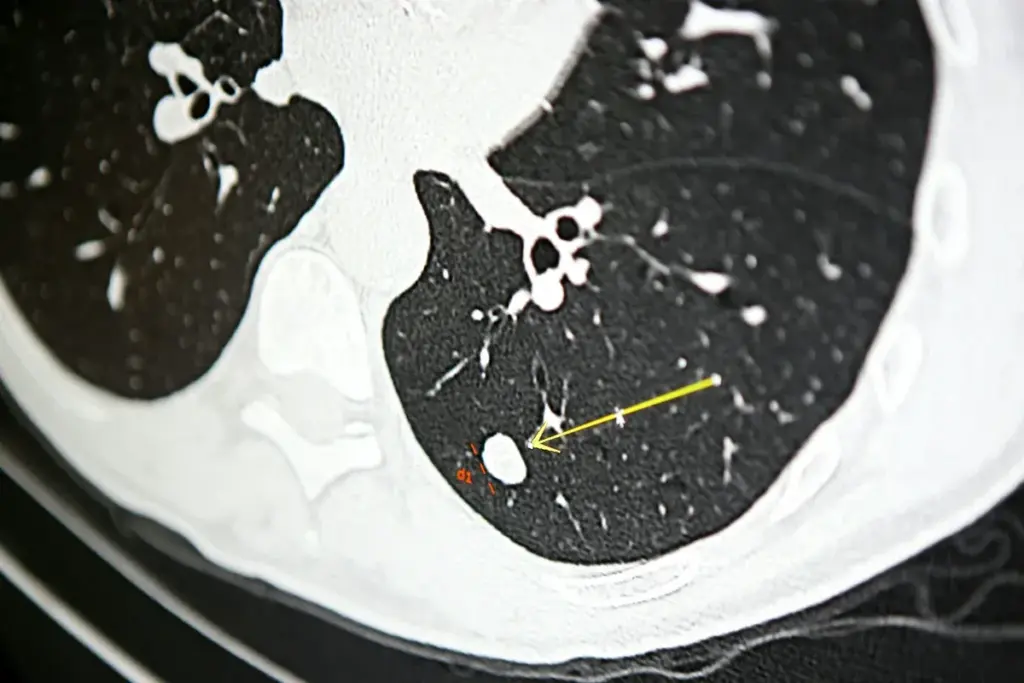

Pneumothorax is a known complication, with rates changing based on needle type and lung health. Our analysis will cover these statistics to show the risks clearly.

Pneumothorax is a serious issue that can happen after CT-guided biopsies. It’s key to know what it is and its effects. We’ll look into its causes, how often it happens, and what it means for those getting lung biopsies.

Pneumothorax means air gets into the space around the lung, causing it to collapse. This can happen during or after a biopsy if the needle hits the pleura. Knowing how it happens helps in reducing its risk.

Incidence Rates in Core Needle Biopsies

Research shows pneumothorax is a common issue with CT-guided lung biopsies. It happens in about 17.6% of cases, with 5.6% needing treatment. This highlights the need for careful planning, precise technique, and close monitoring after the procedure.